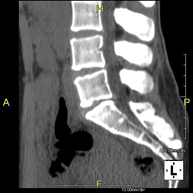

- TC Columna lumbar

Prueba radiológica que consiste en obtener imágenes de las vértebras lumbares de alta definición anatómica mediante el empleo de un equipo de TC (Tomografía Computarizada). Indicaciones: dolor lumbar sin/con irradiación a piernas, dificultad para caminar, traumatismo.